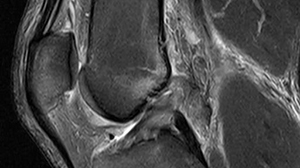

Immediately after the rupture, you are advised to rest, ice, compress and elevate (‘RICE’) the joint. MRI scans are performed to confirm the diagnosis and to see if other damage to the knee joint has occurred.